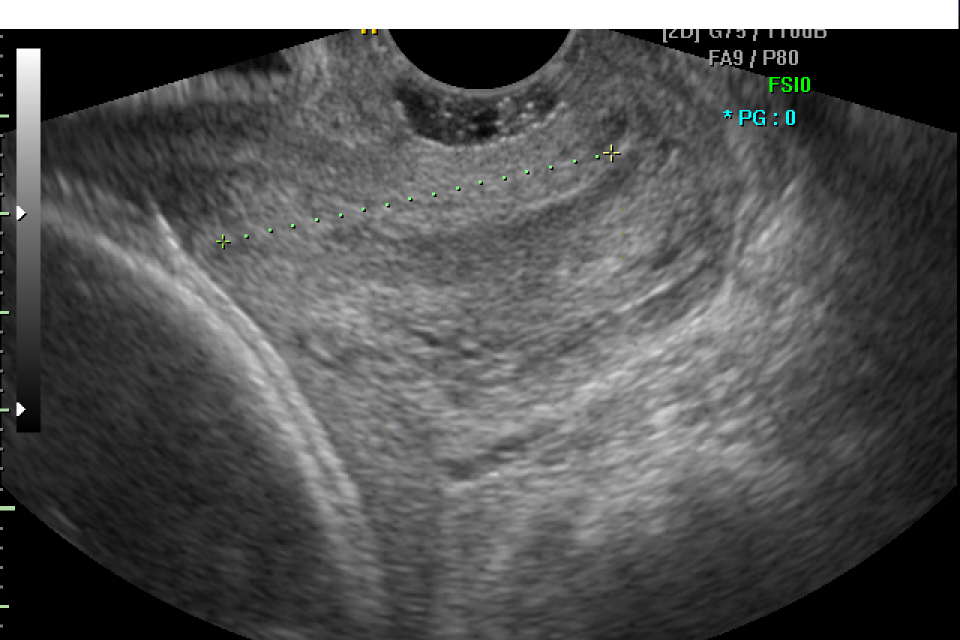

E` una ecografia che valuta principalmente la crescita del bambino, lo stato della placenta, la quantita` di liquido amniotico. Nel corso dell`esame vengono misurati la circonferenza cranica, la circonferenza addominale, il diametro della testa e la lunghezza del femore per poter stimare il peso fetale. Si controlla anche lo stato di benessere degli organi fetale per valutare che la loro formazione segua un decorso regolare rispetto al controllo effettuato durante l`ecografia morfologica. Vengono anche rilevati i movimenti del bambino sia respiratori che del corpo, che insieme alla valutazione del liquido amniotico costituiscono il profilo biofisico fetale, espressione dello stato di benessere del bambino.